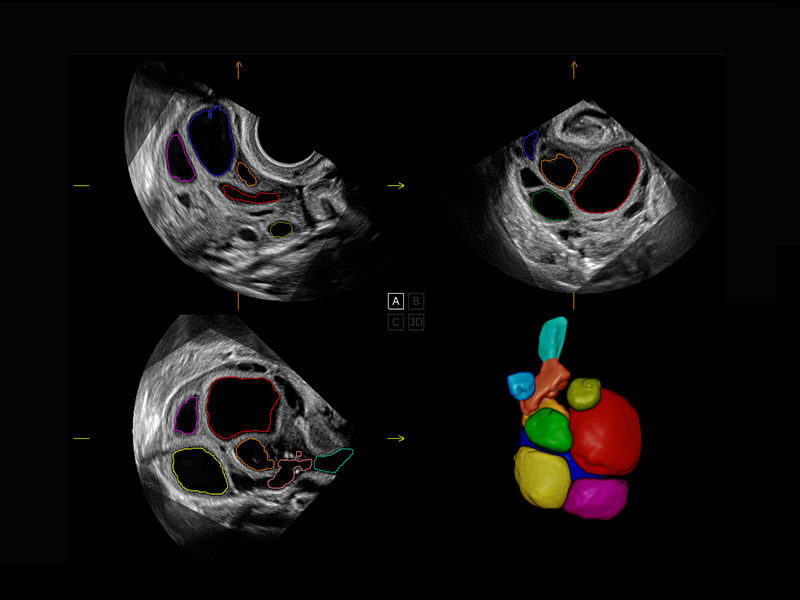

P60提供简单易学易用的高端诊断工具,为您中晚孕筛查提供快速清晰的解剖信息。

1 OFD(HC): 87.03 mm

HC: 251.00 mm

GA: 27w 1d

HC/AC: 96.13 %

2 BPD: 70.56 mm

GA: 28 w 2d

S-Fetus(acq.)

&

S-Fetus(meas.)

S-Fetus能够助您在实时扫查过程中自动识别标准切面、自动测量并录入报告。一个按键,即可快速、高效地获取胎儿生理指标,简化您的产科检查操作。